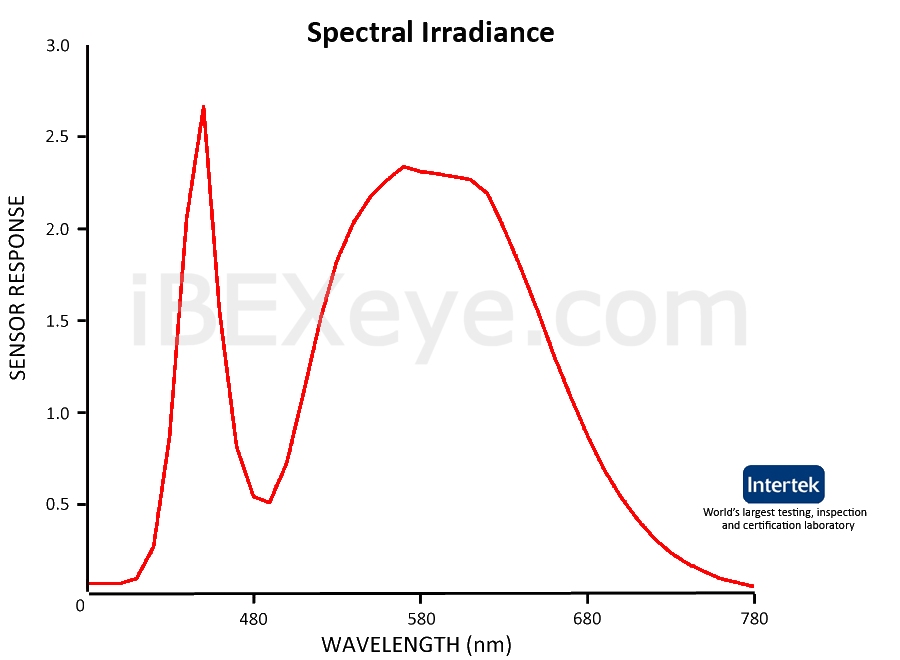

Fine-Tuned Spectrum

The output illumination optimizes irradiance within specific 460-470nm and 570-580nm wavelengths. The result is distinct peaks of irradiance for enhanced viewing of the anterior chamber plus added versatility of improved fundus observation.